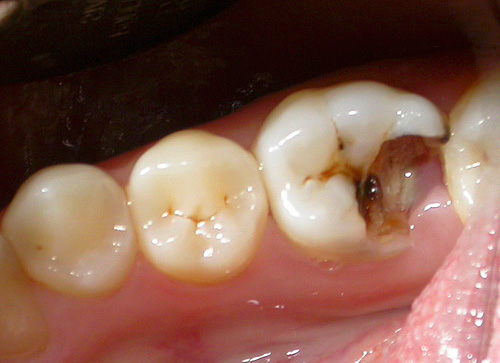

Ad esempio, di seguito nella foto - carie delle fessure. Sui denti, appare sulla superficie masticatoria nelle depressioni naturali chiamate ragadi. In alcuni casi, le linee nere sono così piccole che la sonda dentale e lo sguardo del medico non indugiano su di esse, ma spesso il problema è chiaramente visibile ad occhio nudo:

La carie da fessura è pericolosa perché vaste aree della dentina colpita possono essere nascoste sotto danni allo smalto apparentemente minori. Per una migliore comprensione, guarda un video che mostra schematicamente come la carie penetra nei tessuti dei denti profondi:

E qui ci sono denti con profonde cavità cariate sulle superfici masticatorie: